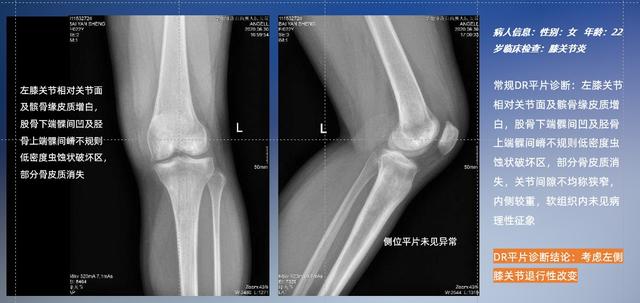

以膝关节疾病检查为例,膝关节在解剖学意义上是一种较为复杂的最大关节,由胫骨上端、股骨下端及髌骨组成。在股骨与胫骨的关节面之间存在两块半月板,分别处于内侧、外侧。膝关节的运动主要为伸、屈,在半屈位时可进行小幅度的旋外、旋内运动。随着现代人们体育生活以及肥胖的增加,膝关节疾病出现高发趋势,特别是关节磨损、膝关节炎与骨关节炎等关节退行性改变,长时间的内翻负荷会造成内侧关节软骨、骨性关节面的磨损。目前针对此类疾病的检查主要为平片下的负重位检查、CT检查以及MRI检查,相较于非负重位检查,负重位检查能更加真实反映膝关节结构中胫骨、股骨、髌骨实际对位关系和关节面的形态特征及关节间隙大小,对膝关节骨关节病诊断准确率高。

普通平片扫描与WR-3D扫描前后诊断结果对比

在负重位状态下,数字化X线三维扫描与重建,能够更好的呈现受检者关节受力改变的状态。必一运动科技创新的WR-3D动态三维影像重建系统,通过数字化X线摄影完成三维扫描并重建三维影像信息,包括断层图像重建、MPR多平面重建、MIP重建以及VR体绘制。其扫描时间短,剂量相较于CT设备大幅缩减,同时成本更低,在临床诊断以及医疗方案制定中具有极大的价值意义。而相较于普通平片下的负重位扫描,负重位动态三维影像重建技术能够避免二维状态下的组织结构重叠、密度分辨率不足、组织解剖结构难以分辨等问题。WR-3D支持多角度的三维观察,能全面的呈现被检查部位在多个角度下的三维影像信息,极大的降低了二维负重位检查带来的漏诊率。